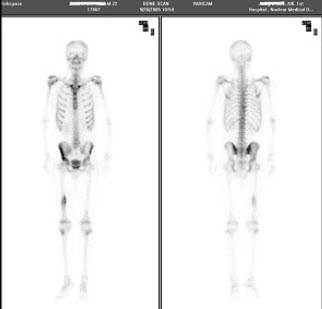

12、单项选择题

女性,78岁,头颅胀痛3个月,肾功能明显受损,HGB56g/L,行全身骨显像,最可能的诊断是()

男性,67岁,阵发性心前区疼痛2年,心电图运动试验阳性,行Tc-MIBI运动-静息心肌显像如图,可能的诊断是()

A.左室前壁、下壁可逆性缺血

B.冠状动脉粥样硬化性心脏病

C.如果冠造阴性,提示X综合征

D.不排除非粥样硬化型冠心病

E.未见心肌缺血